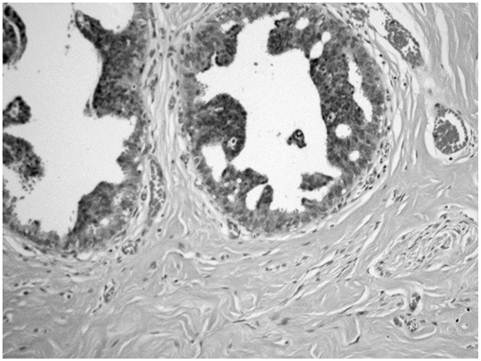

The breast reduction specimen consisted of 426 grams of tissue from the right breast and 490 grams of tissue from the left breast. Gross examination revealed 80% fibrous tissue and 20% adipose tissue without a discrete mass. Extensive histopathologic sampling of the left breast revealed a few foci of lobular carcinoma in situ which was confirmed with a negative E-cadherin immunostain (Figures 4 and 5). Atypical duct cell hyperplasia, cribriform and micropapillary type was also present in a few foci on the left (Figure 6). Both right and left breasts revealed gynecomastia, florid phase.

Figure 4

Monotonous small cells of lobular carcinoma in situ (thin arrows) show pagetoid extension along ducts with undermining of normal ductal epithelium (thick arrow).